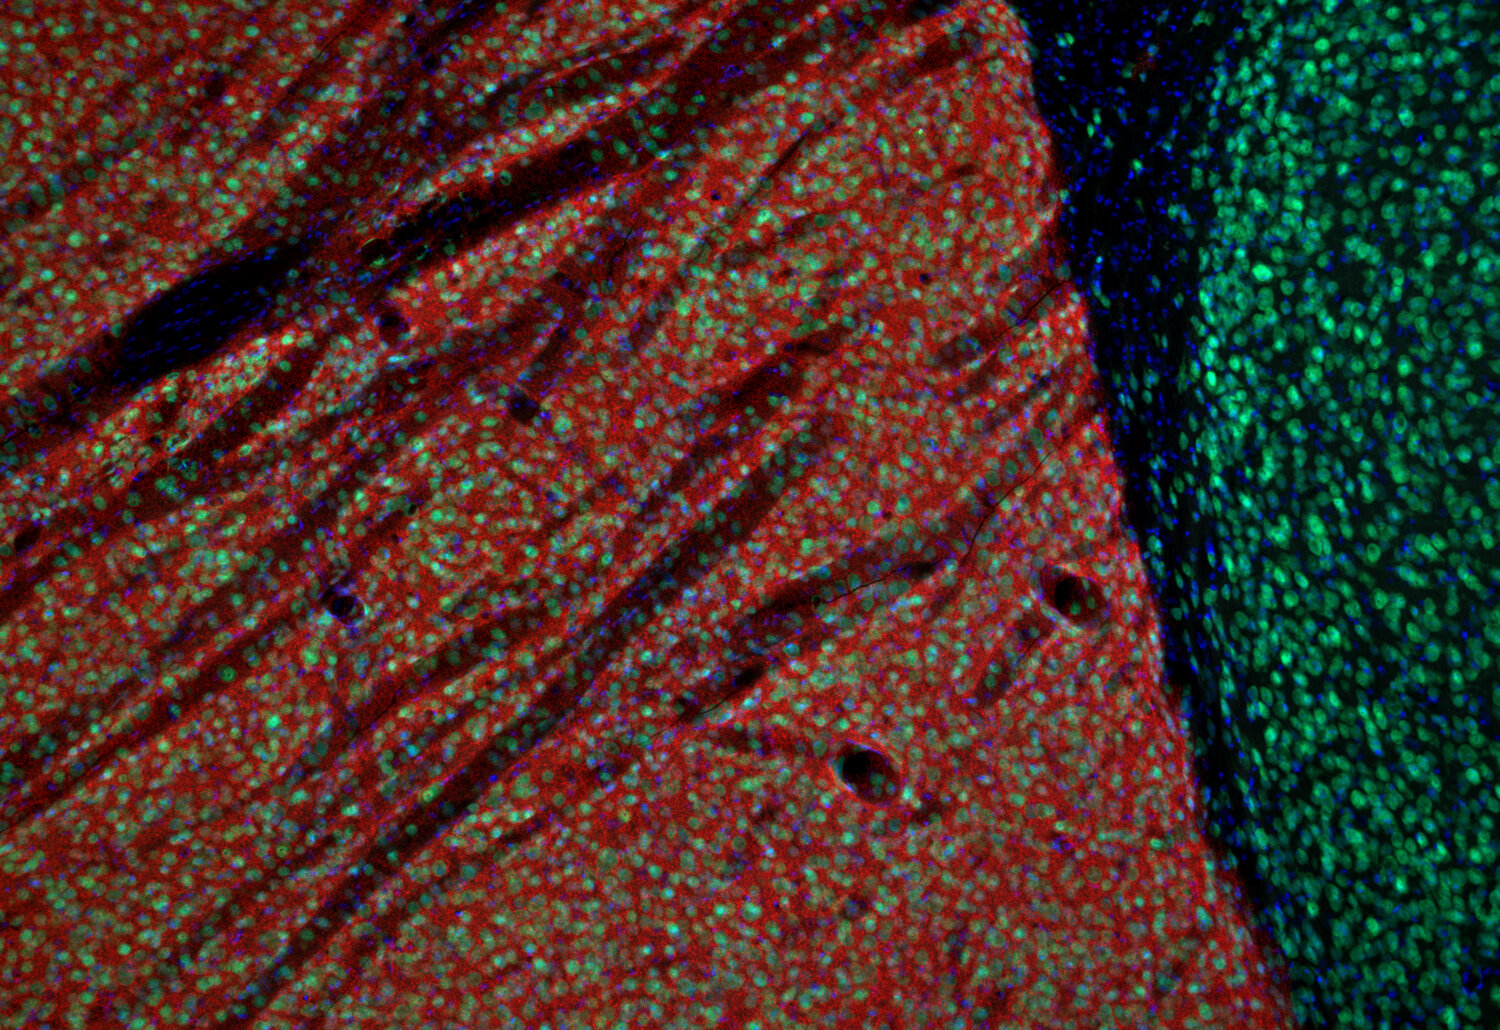

IHC: 1 : 500 gallery

Immunohistochemistry (IHC) on 4% PFA perfusion fixed tissue with 24h PFA post fixation. Immunoreactivity is usually revealed by fluorescence or a chromogenic substrate. Some antibodies require special fixation methods or antigen retrieval steps. For details, please refer to the ”Remarks” section.

Functionally, DAT contributes to the termination of DA signaling by reuptaking DA, thereby controlling both the duration and magnitude of dopaminergic transmission (4). It is predominantly found in dopaminergic neurons and enriched in regions such as the striatum, substantia nigra, and ventral tegmental area, which are associated with motor control and reward mechanisms (5).